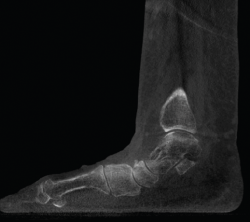

Figura 5. Artropatía de la columna medial en paciente operada de artrodesis astragaloescafoidea.

Figura 6. Artropatía de la columna medial.

- Inestabilidad de la columna medial o inestabilidad tarsometatarsiana. Valoración y estudio de la columna medial en carga (Figuras 5 y 6).